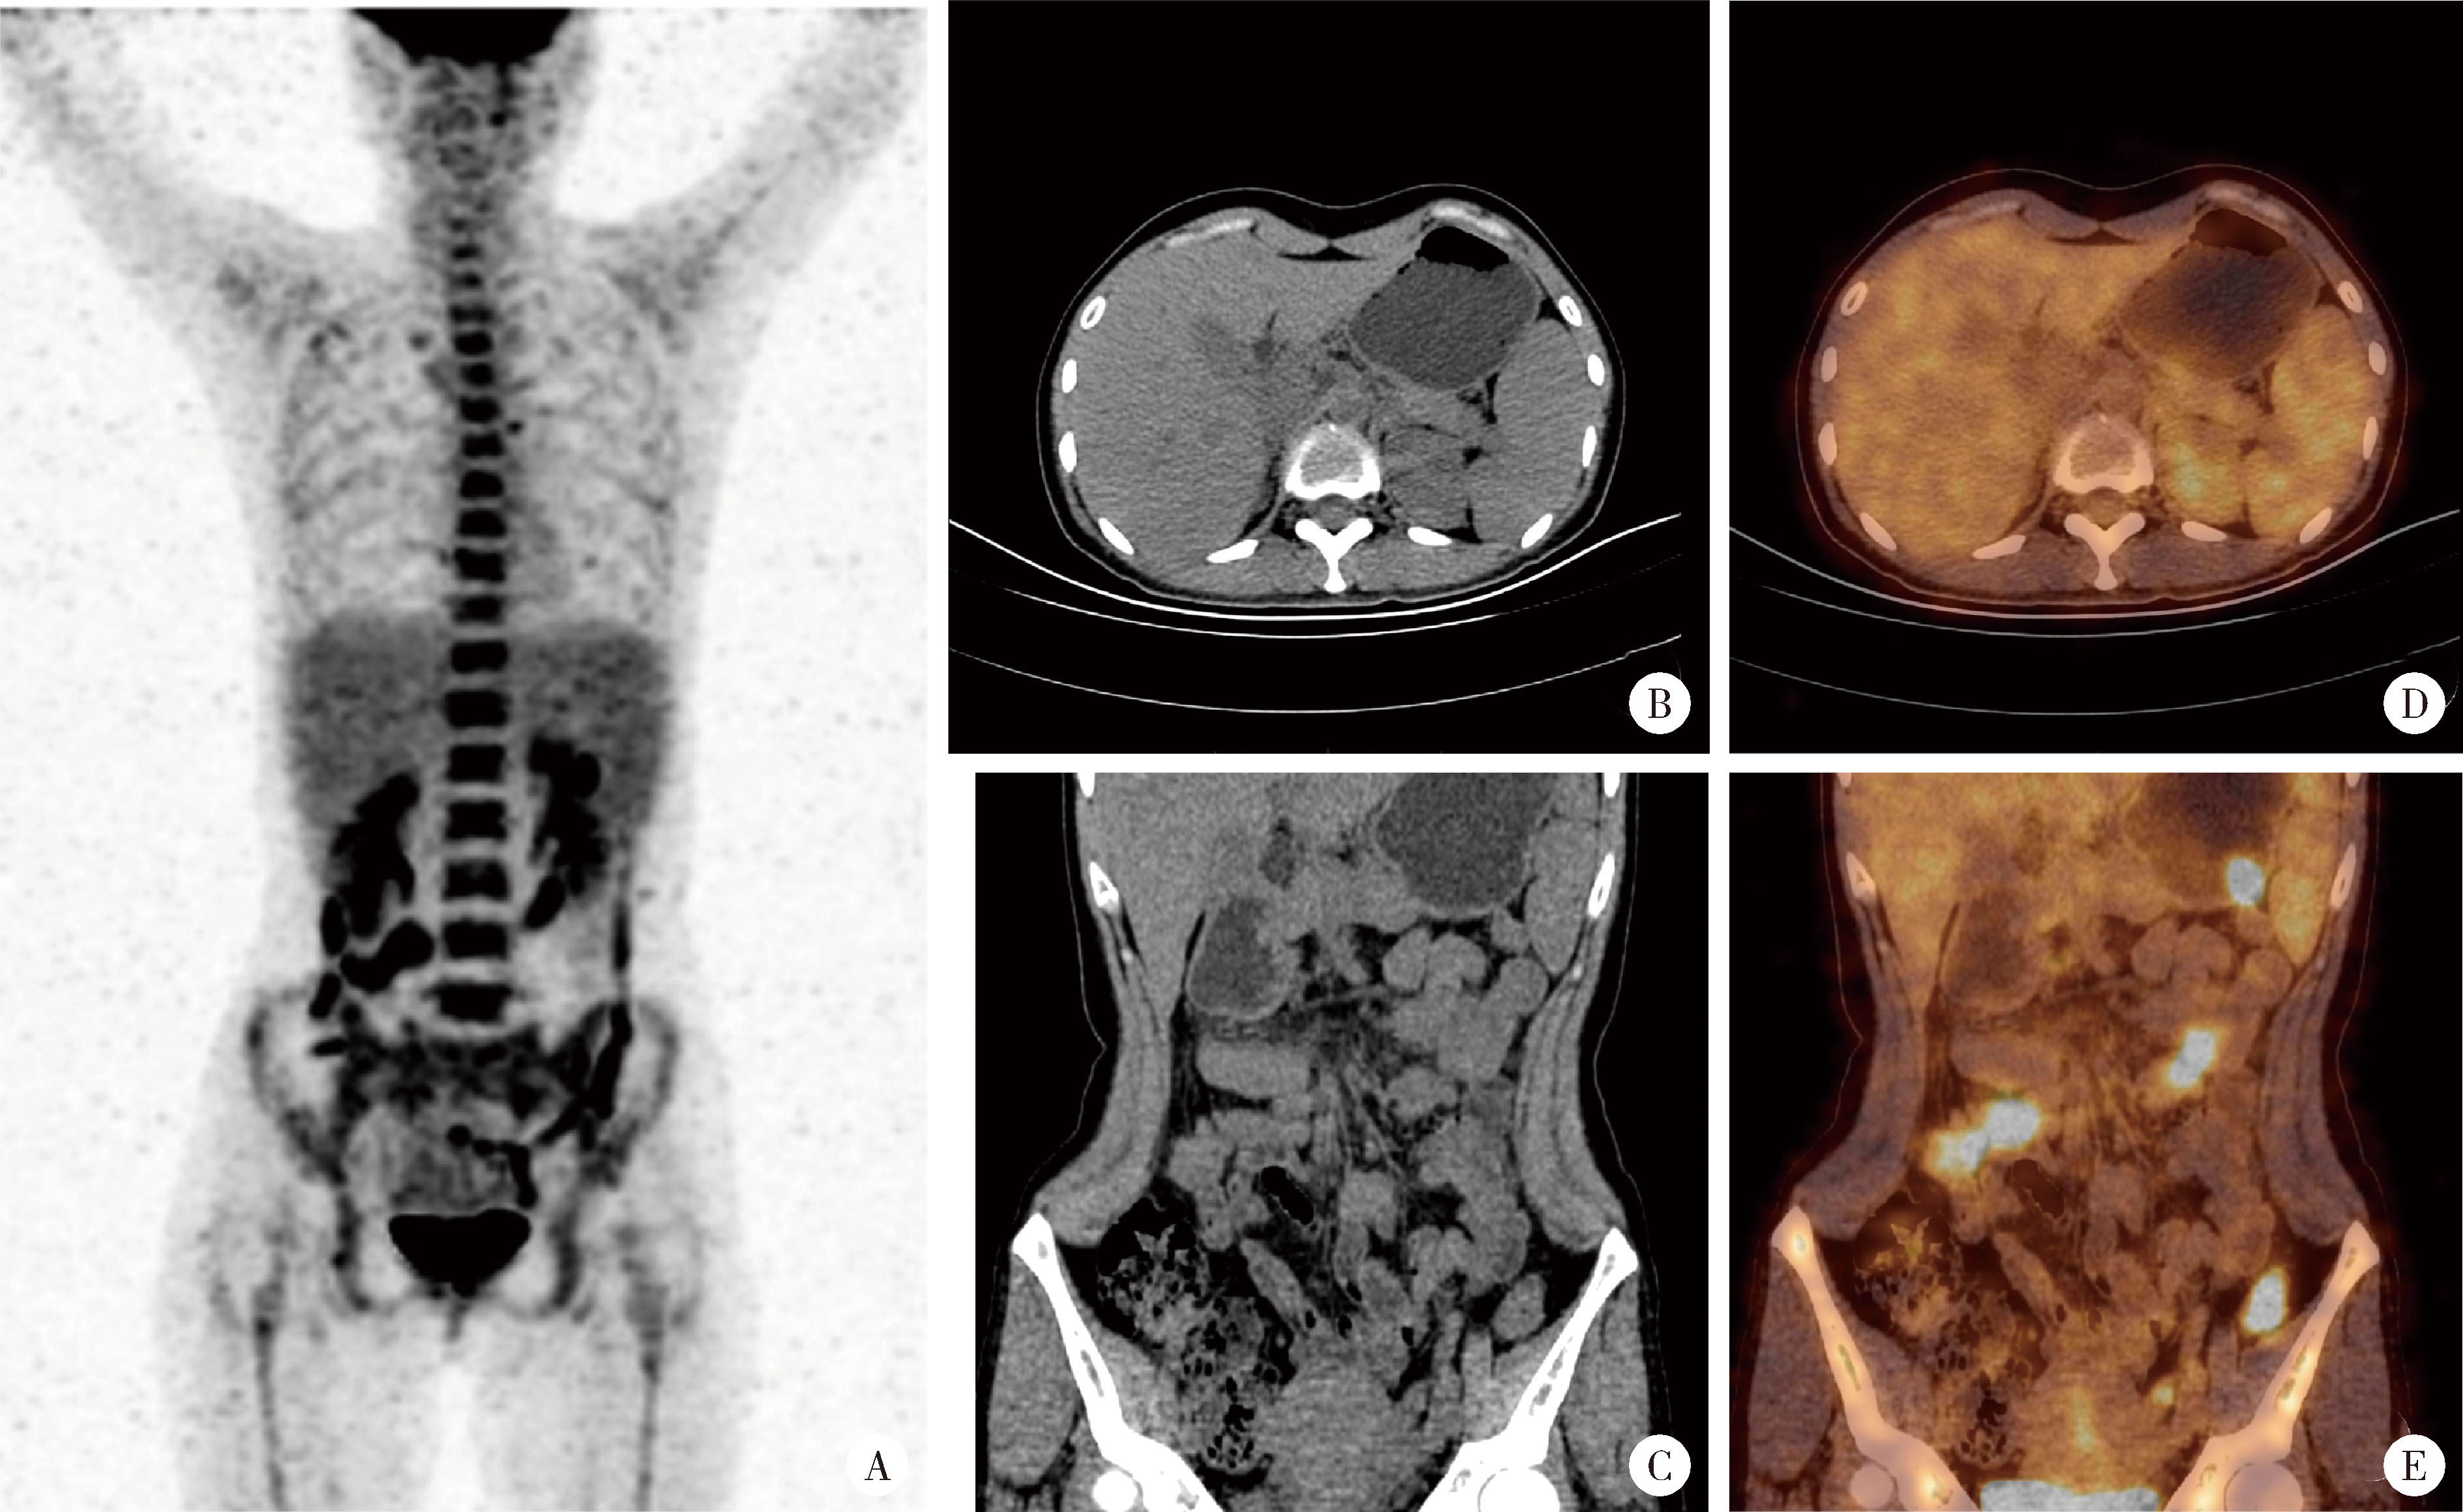

经典型Sweet综合征 18F-FDG PET/CT多脏器异常显像1例

Classical Sweet syndrome with multiple organ lesions by 18F-FDG PET/CT: A case report